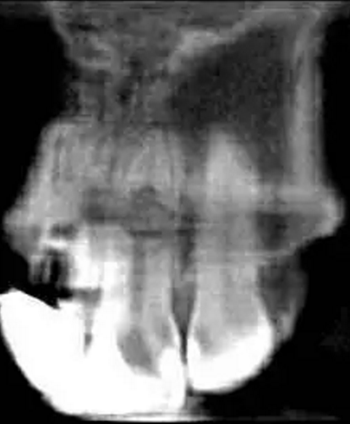

左上中切牙近遠中有牙色充填體,邊緣繼發(fā)齲,牙齒不松動,輕微叩痛,患牙冷測遲鈍,牙齦未見異常。X線片示:充填體周圍繼發(fā)齲壞近髓,根中部大面積低密度影,蟲噬狀,內(nèi)部結(jié)構(gòu)顯示不清晰,根尖周未見異常。錐形束CT(CBCT)顯示根中部內(nèi)吸收多處可疑穿孔,缺損內(nèi)可見菜花狀鈣化物影像

診斷:左上中切牙牙根內(nèi)吸收。治療計劃:左上中切牙根管治療,全冠修復(fù)。 治療過程:患者知情同意。使用含1/100,000腎上腺素的4%鹽酸阿替卡因(碧蘭麻,艾龍)局部浸潤麻醉,橡皮障隔濕。去腐未盡露髓,露髓孔出血多。開髓,使用10#不銹鋼K銼(MANI,日本)探查根管,根管中段有鈣化物阻擋,不能達到牙根全長(圖3A)。在顯微鏡下(Leica M400E,萊卡, 德國) 使用超聲尖(E1根管治療超聲尖,啄木鳥公司,中國)通開,采用根管長度測量儀(Root ZX, Morita公司,日本)加診斷絲片法(圖1B)測量根管長22 mm。使用控制扭矩馬達(X-smart,登士柏)和鎳鈦旋轉(zhuǎn)器械(Hero 642, Micromega)根管預(yù)備,根管預(yù)備過程中使用5.25%次氯酸鈉溶液沖洗。 根備完成后使用超聲蕩洗根管,5.25%次氯酸鈉溶液3 分鐘, 17% EDTA溶液1分鐘。干燥根管,使用螺旋充填器根管內(nèi)封氫氧化鈣糊,氧化鋅丁香油水門汀暫封。1周后患者復(fù)診,患者述無術(shù)后不適,檢查暫封完好,無叩痛,不松,牙齦無紅腫瘺管。使用橡皮障隔濕,去除暫封物,超聲蕩洗根管,5.25%次氯酸鈉溶液3 分鐘, 17% EDTA溶液1分鐘。干燥根管,牙膠尖(達雅鼎,中國)和必蘭根充糊劑(Cortisomol, 艾龍公司,法國)熱垂直加壓法根管充填。術(shù)后片顯示根充恰填,可見牙膠/糊劑被壓入鈣化物周圍和內(nèi)部縫隙內(nèi)